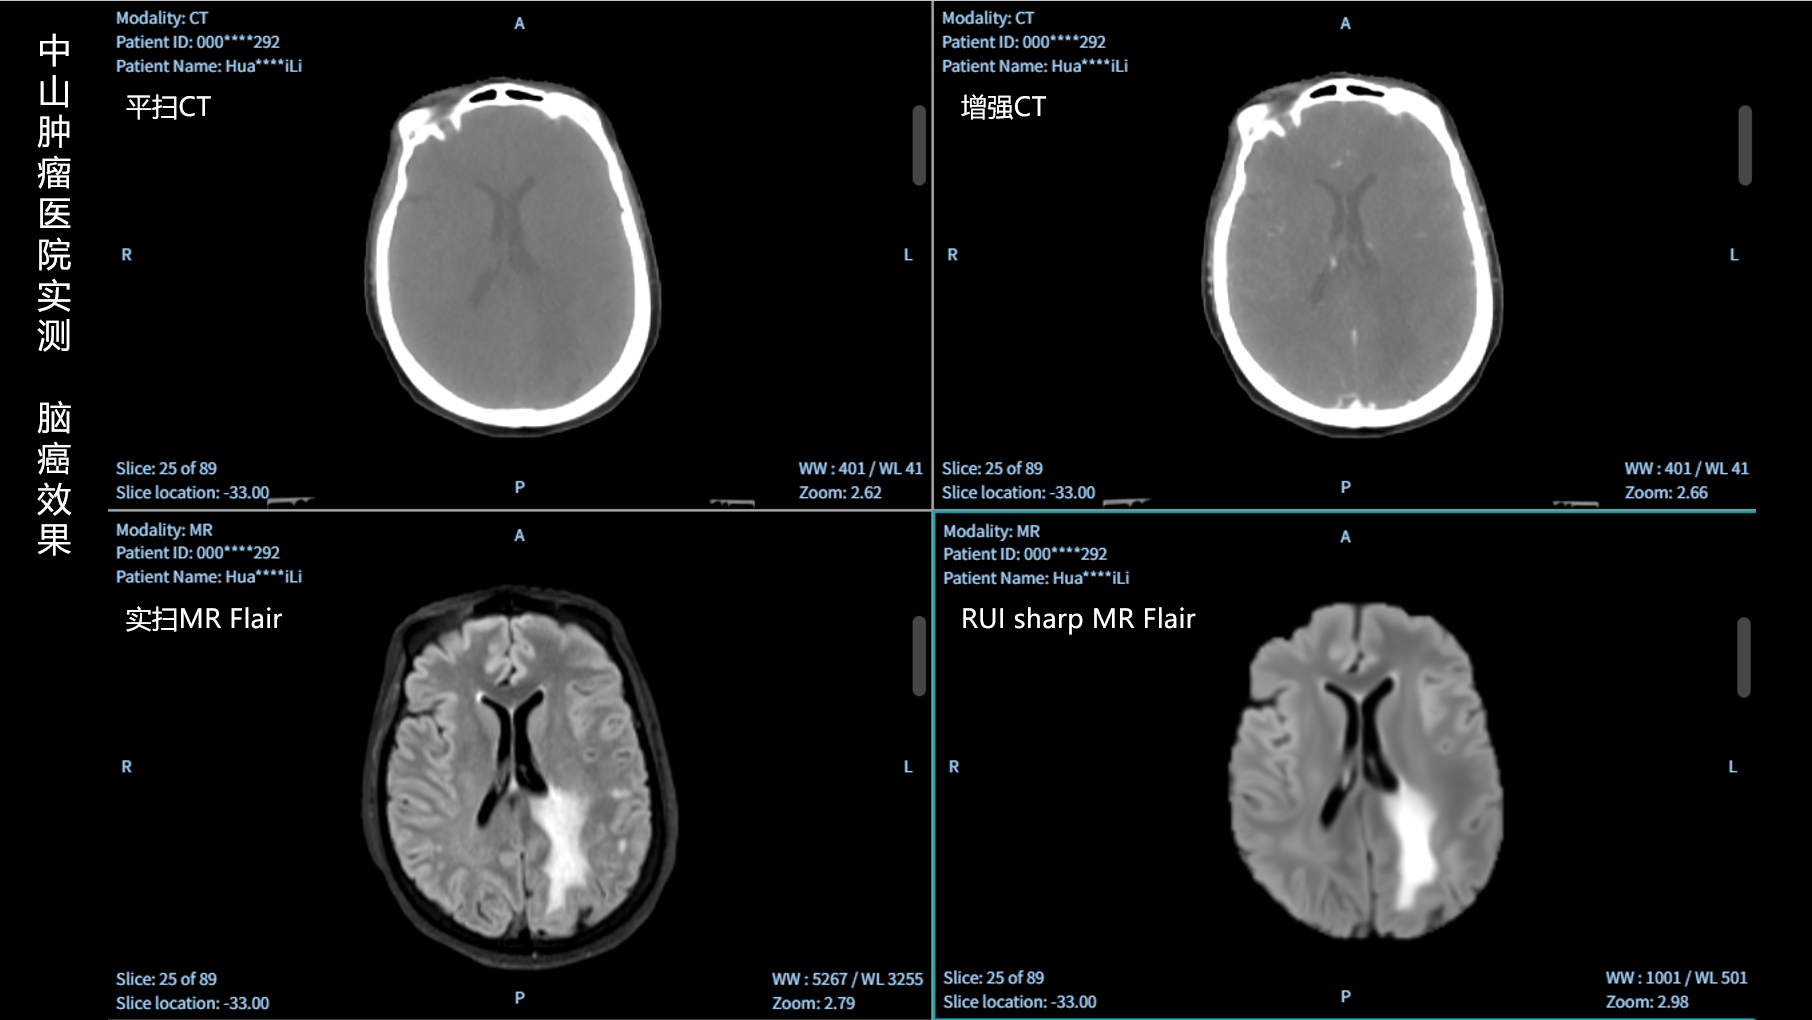

RUI sharp H(锐影)可在不依赖MRI的前提下,显著提升头部CT图像的软组织分辨率,为临床提供更高质量的辅助信息,尤其适用于MRI资源受限或较难配准的头颈部放疗感兴趣区勾画场景。

可大幅提高头部CT影像软组织分辨率,使肿瘤和周边器官显示更清晰,为放疗靶区勾画提供参考。

无需图像配准,CT和锐影图像同源,可匹配、叠加、"淡入淡出"显示。

实测效果